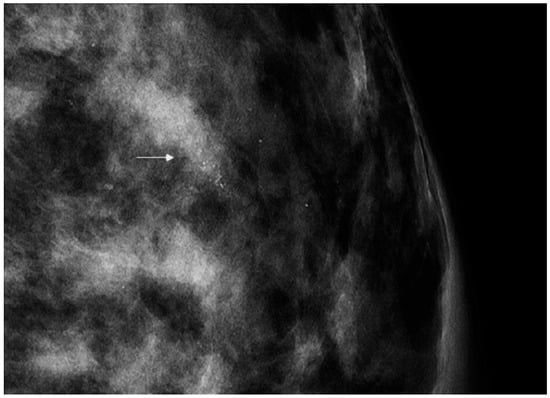

All the lesions undergoing stereotactic VABB presented as microcalcifications. Before each stereotactic VABB, two projection mammograms were performed in order to assess the precise extension of the lesion (Figure 1).

Figure 1.

Full-field digital mammography showing a small cluster of pleomorphic microcalcifications (arrow) with a biopsy-proven histopathological result of low-grade ductal carcinoma in situ.